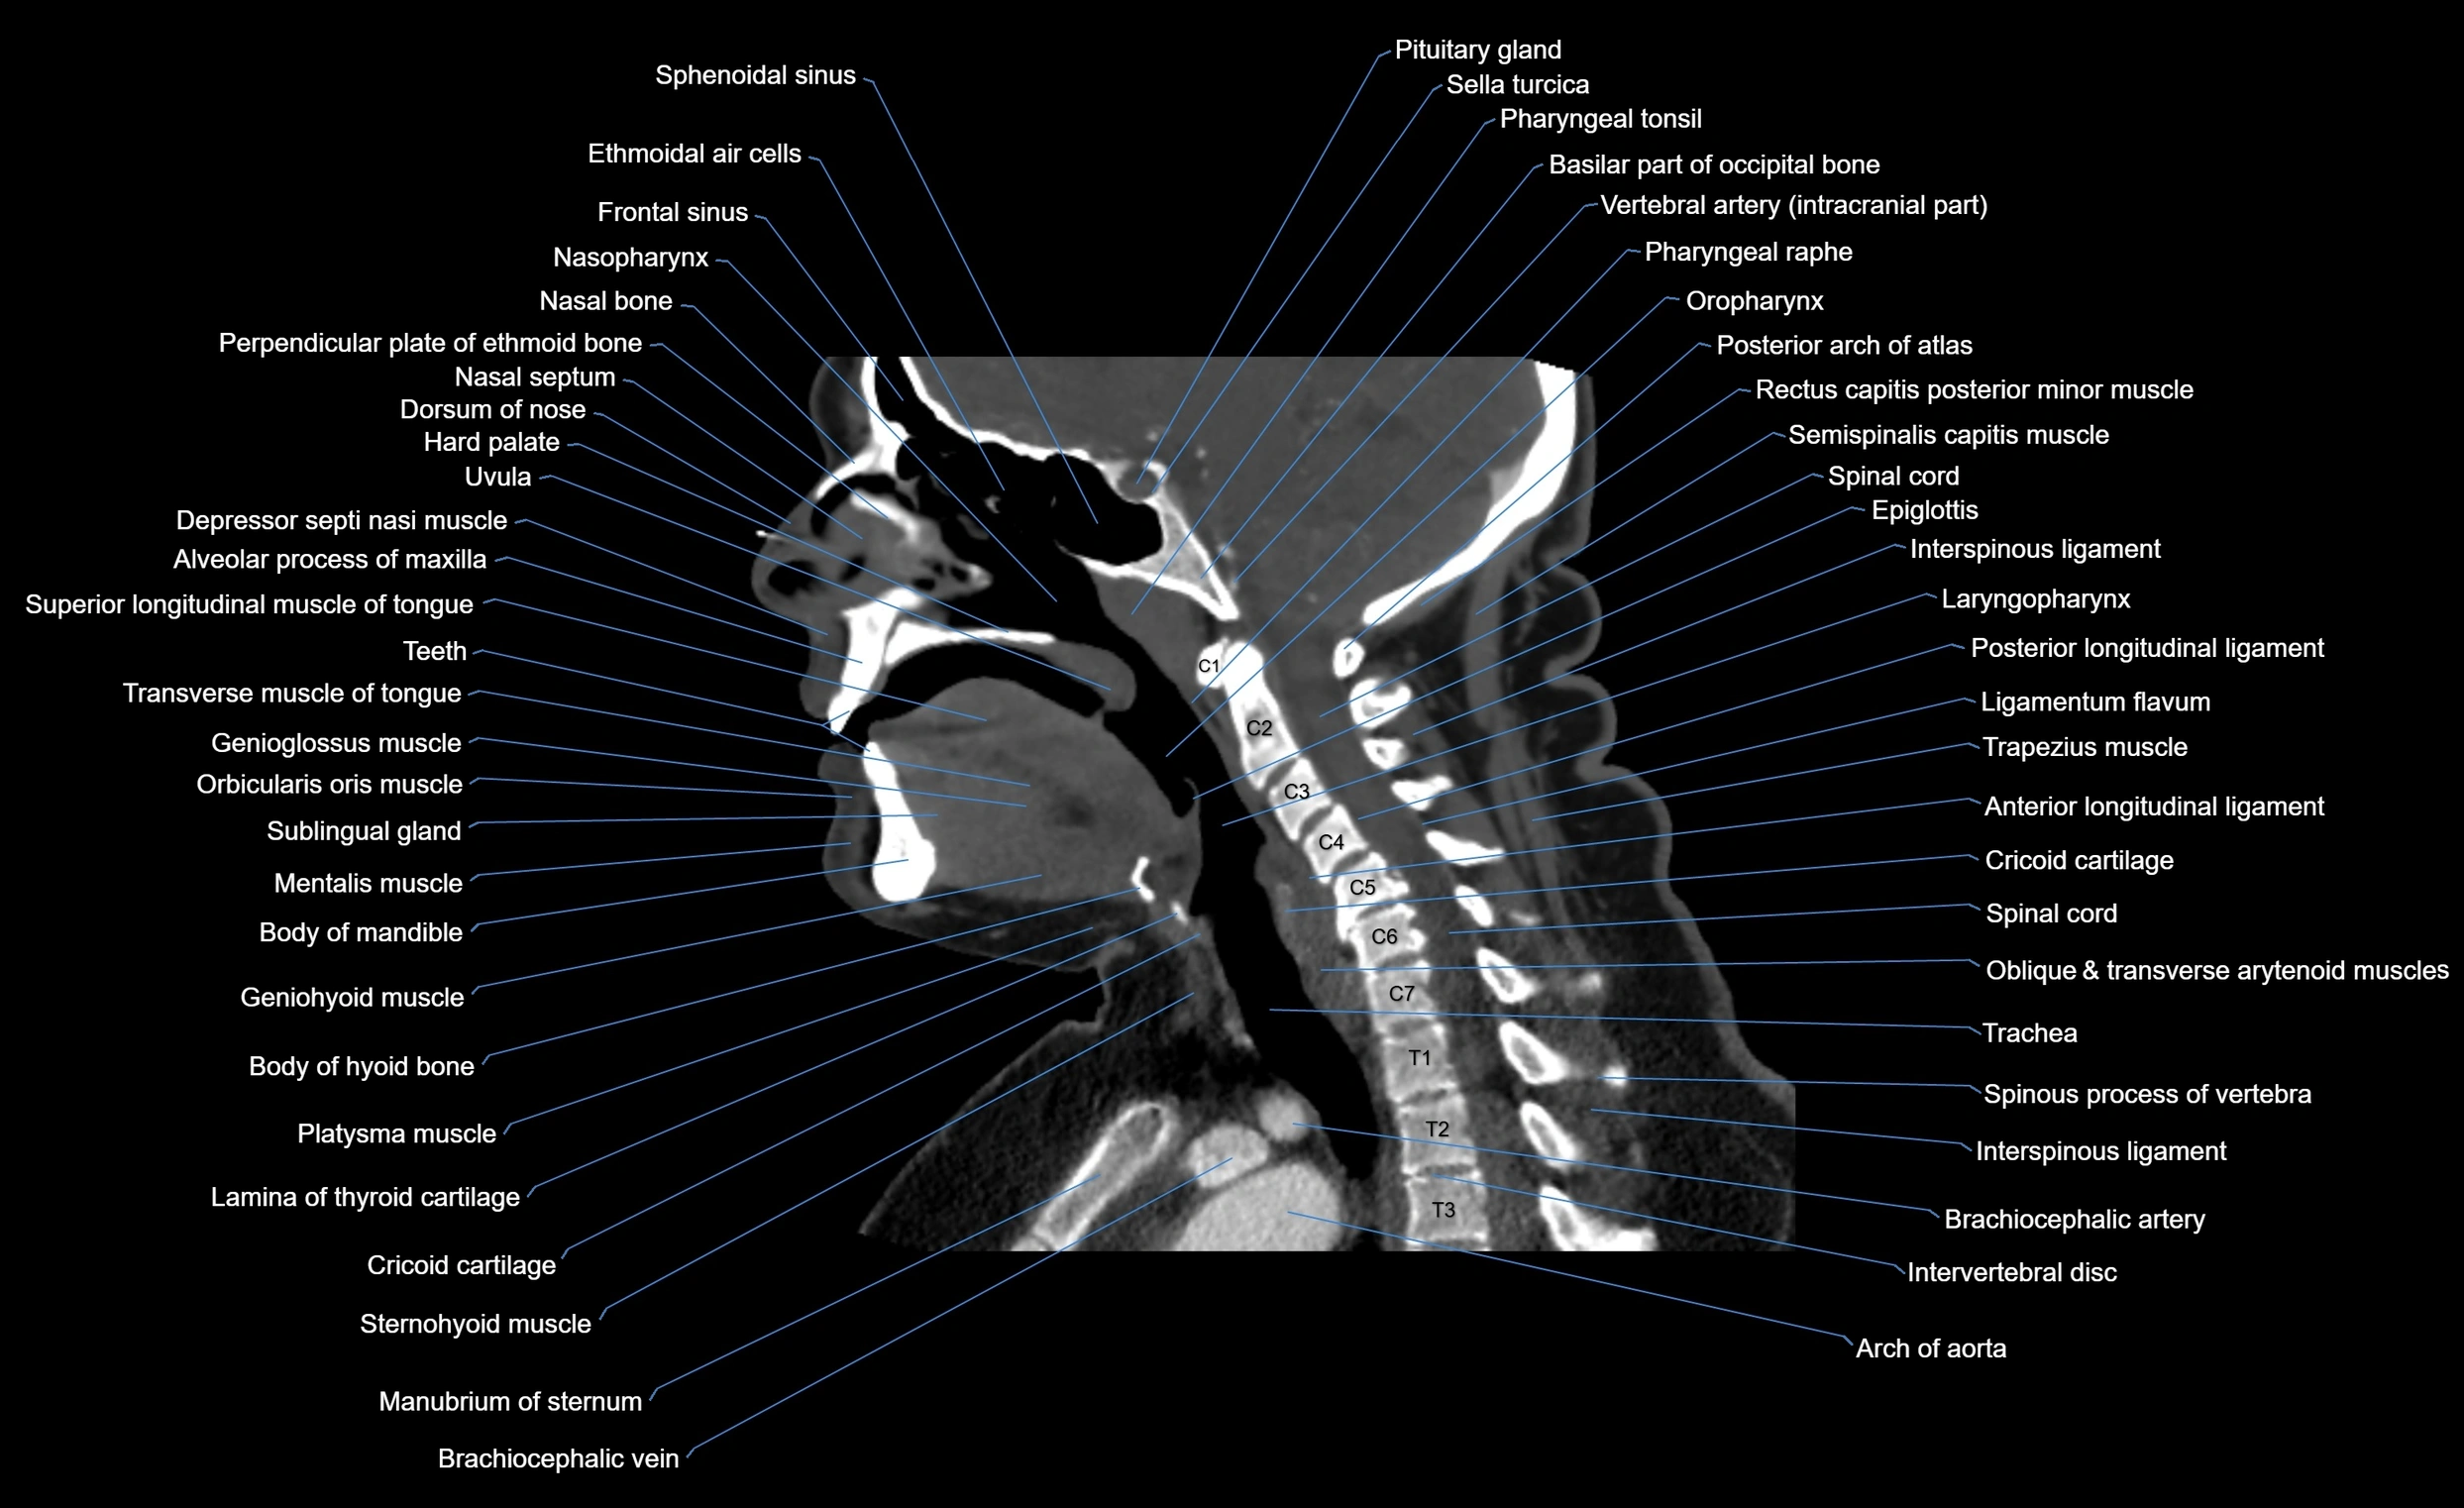

- Anterior longitudinal ligament

- Epiglottis

- Interspinous ligament

- Intervertebral Disc

- Laryngopharynx

- Ligamenta flava (Ligamentum flavum)

- Posterior longitudinal ligament

- Spinal cord

- Trachea